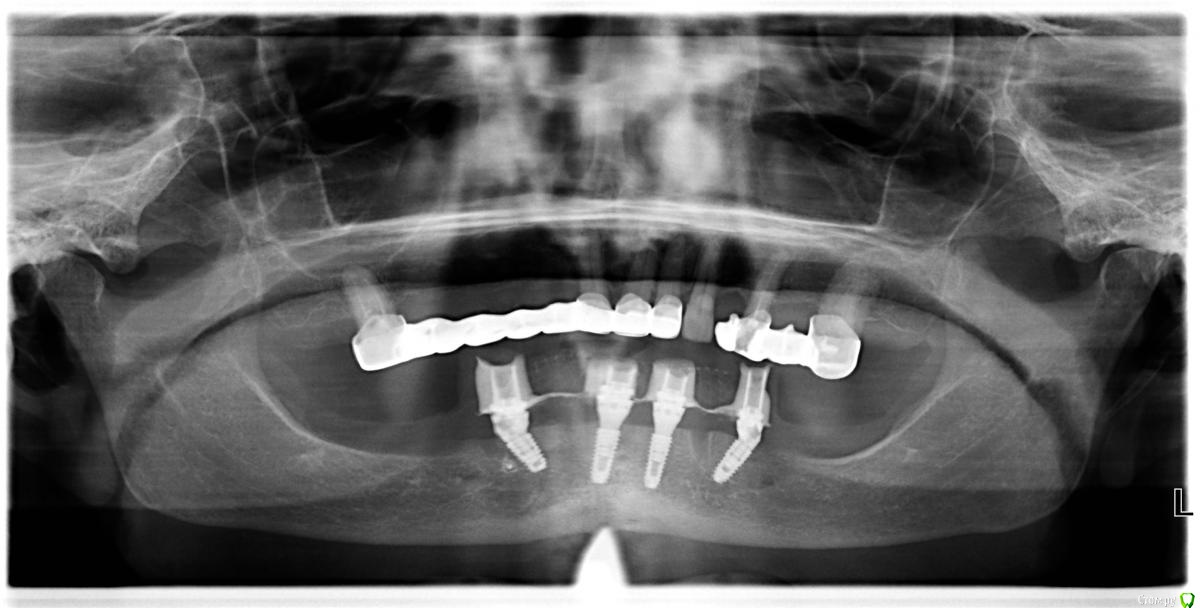

Dman Опубликовано 22 августа, 2019 Поделиться Опубликовано 22 августа, 2019 (изменено) Всем привет. Закончил кейс, который продвигался очень сложно всю дорогу, делюсь)Пациент 70 лет. Состояние здоровья соответствующее. Во рту так Слепки, кт, планирование, изготовление шаблона, изначально хотел идти на оллинфо, проектировщик шаблона долго не хотел делать под дистальные имланты длину 4*13(очень широкая резцовая петля). Уговорил, шаблон готов, поехали.Сверлится очень плохо, несмотря на просьбу добавить пару фиксирующих пинов их нет, да и места куда их там уместить не особо. В итоге из 4 пилотных 3 мимо. раскрываюсь, редукция, поднялось давление 160, при редукции бьют фонтанчики из сосудов в области центральных резцов, периодически коагулирую их лазером. Засверливаюсь дистально ии! льет кровища как из шланга. Меняю план, ставлю дистально 4*8,5. Ушиваюсь. Панорама Сразу слепок, протез уже готов под нагрузку, техник готовит протез.Вид на следующий день Перебазировываю во рту, прикручиваю. Панорама На этом все, вторая часть в ортопедическом разделе. Буду рад услышать советы. Изменено 22 августа, 2019 пользователем Dman 7 Ссылка на комментарий

pit Опубликовано 30 августа, 2019 Поделиться Опубликовано 30 августа, 2019 Всем привет. Закончил кейс, который продвигался очень сложно всю дорогу, делюсь)Пациент 70 лет. Состояние здоровья соответствующее. Во рту так Сверлится очень плохо, несмотря на просьбу добавить пару фиксирующих пинов их нет, да и места куда их там уместить не особо. В итоге из 4 пилотных 3 мимо. раскрываюсь, редукция, поднялось давление 160, при редукции бьют фонтанчики из сосудов в области центральных резцов, периодически коагулирую их лазером. Засверливаюсь дистально ии! льет кровища как из шланга. Меняю план, ставлю дистально 4*8,5. На этом все, вторая часть в ортопедическом разделе. Буду рад услышать советы. 1. Я не совсем понимаю почему нельзя было установить 4х11,5 или 4х13, если установлены 4х8,5??? Кровоточивость не мешает сверлению, вопрос всего в 3-4 мм.2. Дистальные импланты надо было установить на 5 мм дистальнее, судя по ОПТГ. Для этого нужно было откинуть лоскуты и выделить оба ментальных нерва.3. В клинике всегда нужно иметь нифедипин, 20 мг под язык - экстренная помощь при резком повышении АД. Хотя 160 не такая высокая цифра, чтобы говорить о ужасном кровотечении при типовой операции4. Фонтанчики крови часто бывают при редукции и при нормальном давлении. С ними лучше всего бороться алмазным шариком на больших оборотах без воды или локальным сдавлением кости щипцами.5. В конце концов можно было остановить операцию, назначить а/б, гипотензивные препараты, режим и через 2-3 дня все доустановить.6. Отвечу здесь по ортопедии. Даже в Вашем решении можно было выполнить несъемную конструкцию. из 12-и зубов с компромиссными молярами, длина имплантов имеет решающее значение только при немедленной нагрузке. Ссылка на комментарий

Dman Опубликовано 30 августа, 2019 Автор Поделиться Опубликовано 30 августа, 2019 1. Я не совсем понимаю почему нельзя было установить 4х11,5 или 4х13, если установлены 4х8,5??? Кровоточивость не мешает сверлению, вопрос всего в 3-4 мм.2. Дистальные импланты надо было установить на 5 мм дистальнее, судя по ОПТГ. Для этого нужно было откинуть лоскуты и выделить оба ментальных нерва.3. В клинике всегда нужно иметь нифедипин, 20 мг под язык - экстренная помощь при резком повышении АД. Хотя 160 не такая высокая цифра, чтобы говорить о ужасном кровотечении при типовой операции4. Фонтанчики крови часто бывают при редукции и при нормальном давлении. С ними лучше всего бороться алмазным шариком на больших оборотах без воды или локальным сдавлением кости щипцами.5. В конце концов можно было остановить операцию, назначить а/б, гипотензивные препараты, режим и через 2-3 дня все доустановить.6. Отвечу здесь по ортопедии. Даже в Вашем решении можно было выполнить несъемную конструкцию. из 12-и зубов с компромиссными молярами, длина имплантов имеет решающее значение только при немедленной нагрузке. 1 лило реально как из шланга, + там резцовая петля очень широкая думаете можно было оставить верхушку импланта в ней, или пройти насквозь?2 найду кт гляну, но планировал не один, видимо были причины3 не слышал про такой, найдем и купим4 первая объемная редукция, ранее не слышал что это норма(5 не думал что получится что-то лучше, в связи с резцовой петлей6 за неимением опыта(копылов давал данные что дистальные меньше 11мм, неблагоприятный прогноз), решил перестраховаться, возможно неправ огромное спасибо за советы, будем расти Ссылка на комментарий